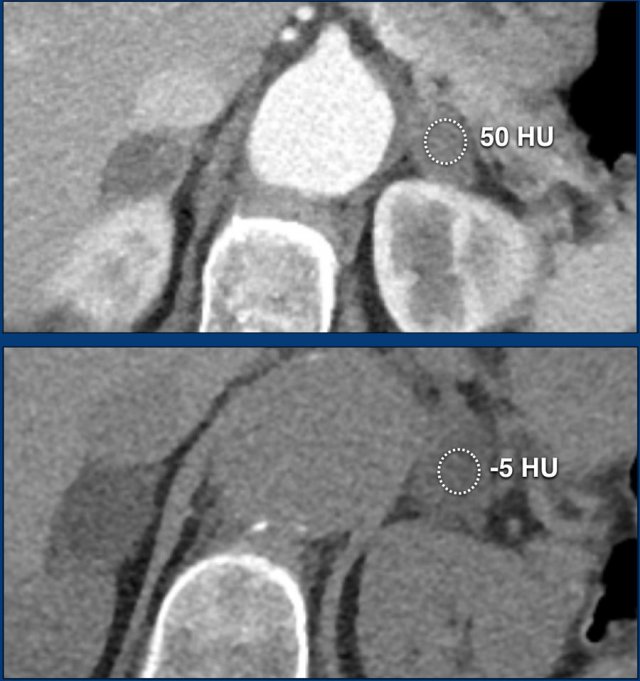

Bilateral adrenal incidentalomas were identified in a 64-year-old patient undergoing CT for evaluation of an abdominal aortic aneurysm.

Arterial phase imaging revealed bilateral adrenal lesions with a density of 50 HU.

Subsequent non-enhanced CT, performed several days later, demonstrated densities <10 HU in both adrenal glands, confirming the diagnosis of lipid-rich adenomas.